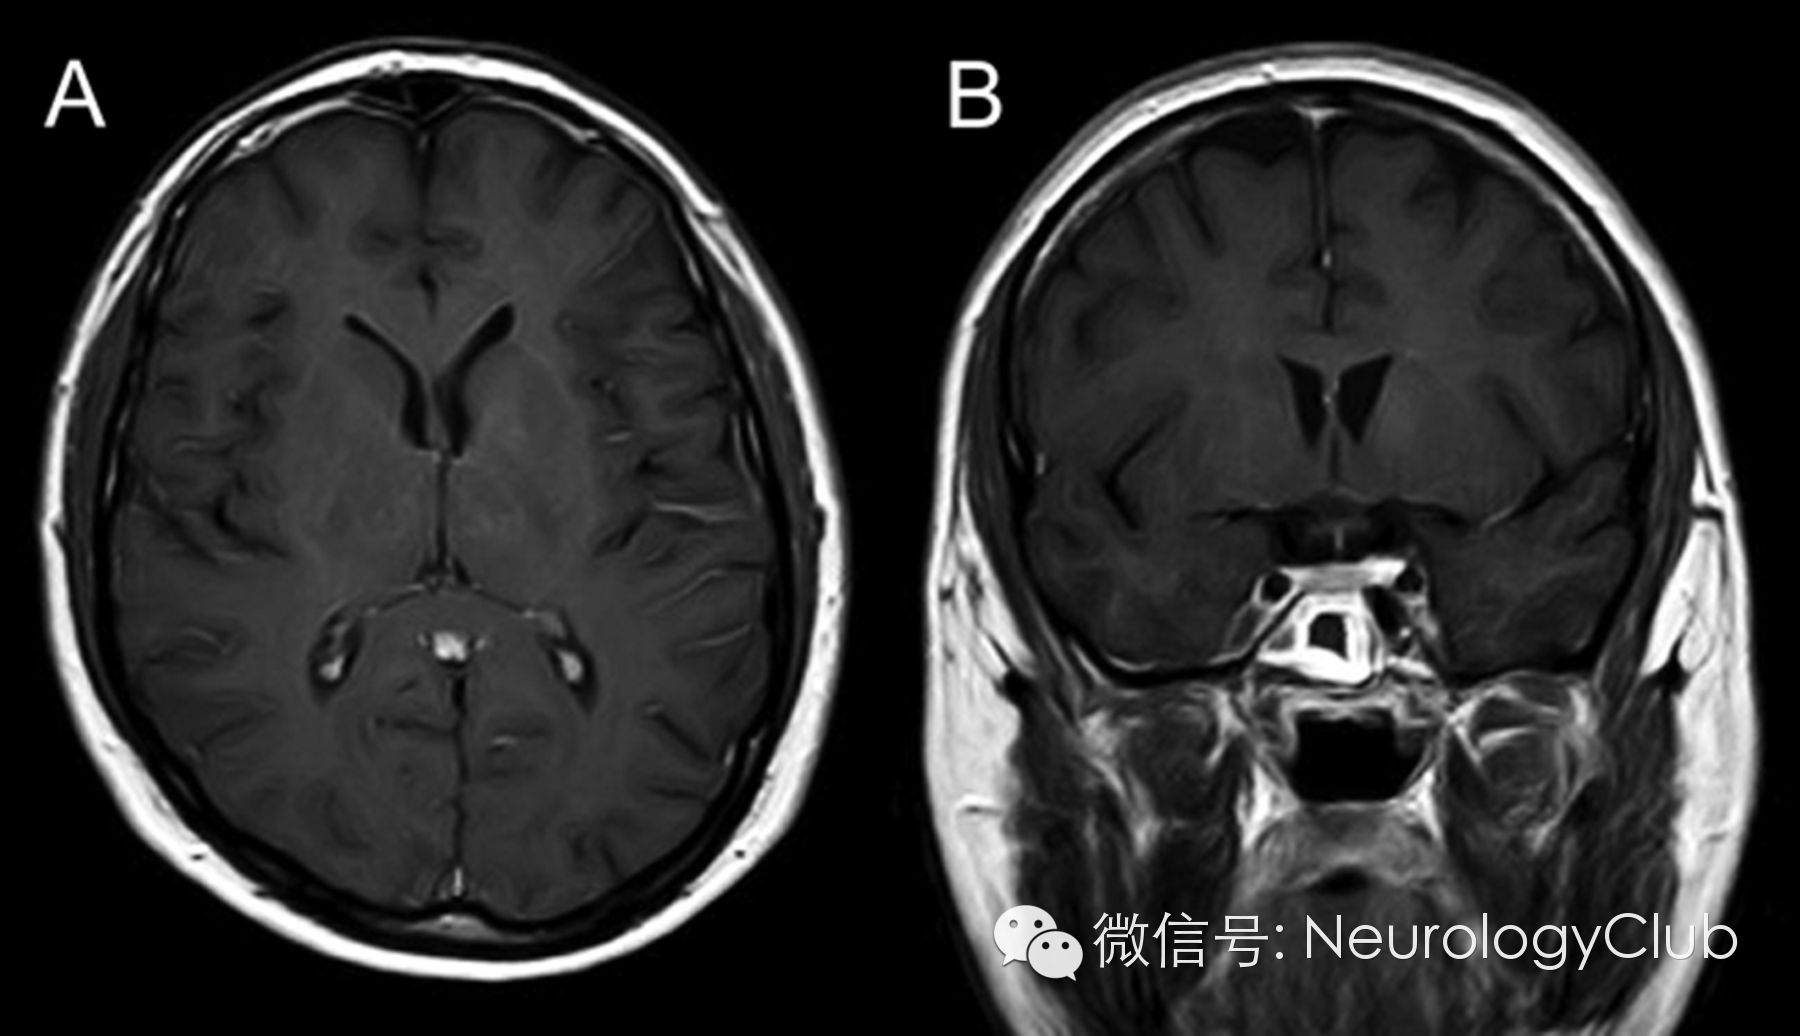

30岁男性,表现为面-臂肌张力障碍发作(faciobrachial dystonic seizures,FBDS)。发作期和发作间期的脑电图正常。脑脊液化验无殊。头颅MRI示左侧尾状核和苍白球强化病灶(图1)。血清LGI-1(富亮氨酸胶质瘤失活1蛋白)抗体阳性。全身CT扫描未发现恶性肿瘤。患者行5个周期的血浆置换后再接受长期的激素治疗,完全恢复。5月后复查头颅MRI,发现病灶强化信号减弱(图2)。LGI-1是一种与电压门控钾离子通道相关的分泌蛋白,在新皮质与海马区高度表达。LGI-1突变见于合并听觉症状的常染色体显性遗传颞叶癫痫(autosomal dominant partial epilepsy with auditory features,ADPEAF)。本例患者无ADPEAF的临床症状。关于FBDS是一种癫痫发作还是肌张力障碍仍存在争论。本例患者基底节区受累可与这一争议相关。

图2:治疗后复查增强MRI